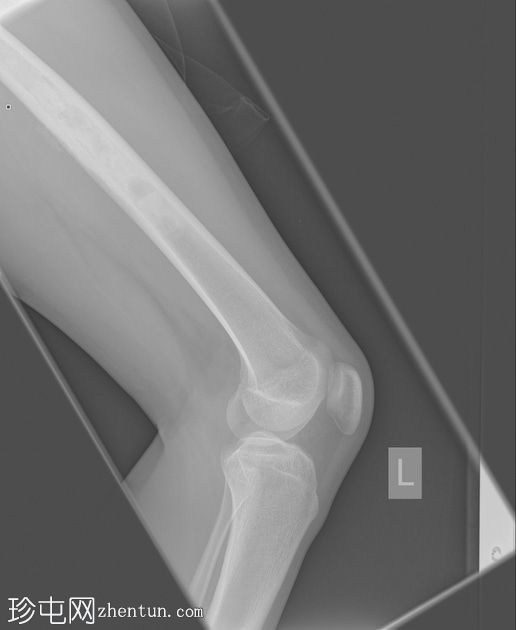

X光片

正面

侧面

斜面

左股骨中段可见边界不清的硬化区域,伴有宽阔的过渡区和虫蛀状外观。

邻近软组织可见小块钙化灶。无骨折或脱位。